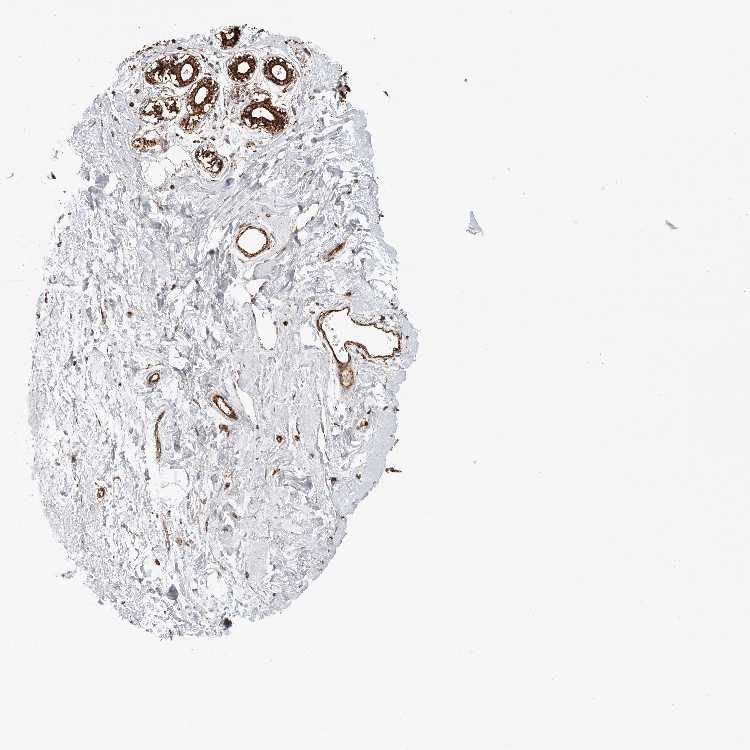

BREAST - Antibody stainingi

Antibody staining in the annotated cell types in the current human tissue is reported as not detected, low, medium, or high, based on conventional immunohistochemistry profiling in selected tissues. This score is based on the combination of the staining intensity and fraction of stained cells.

Each image is clickable and will lead to virtual microscopy that enables deeper exploration of all samples and also displays staining intensity scores, fraction scores and subcellular localization as well as patient and tissue information for each sample.

Antibody HPA026436Antibody HPA026451Antibody HPA026501

Adipocytes MediumLowNot detected

Glandular cells HighMediumNot detected

Myoepithelial cells HighMediumMedium